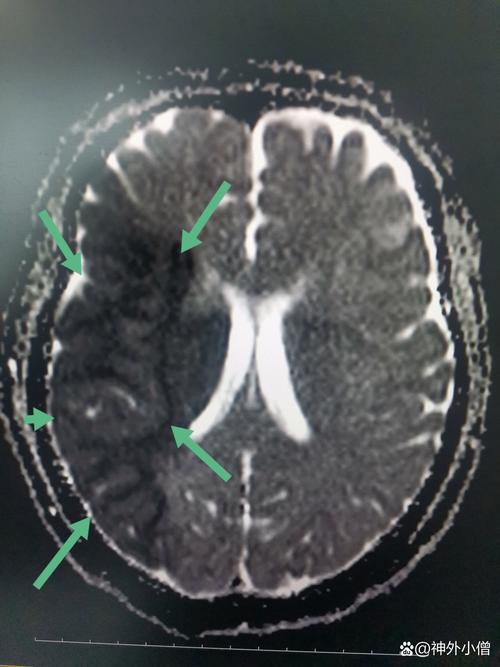

大面积脑梗,通常指颈内动脉系统主干(如大脑中动脉)发生严重闭塞,导致其供应的大脑区域(如整个大脑半球)发生广泛、严重的缺血和坏死。

(图片来源网络,侵删)

- 头颅CT扫描: 这是最关键的第一步,目的是排除脑出血(因为脑出血和脑梗的治疗原则完全相反),在发病早期,CT可能看不到明显的梗塞灶,但可以排除出血,为下一步溶栓或取栓提供依据,CT也能初步评估是否有脑水肿和占位效应。